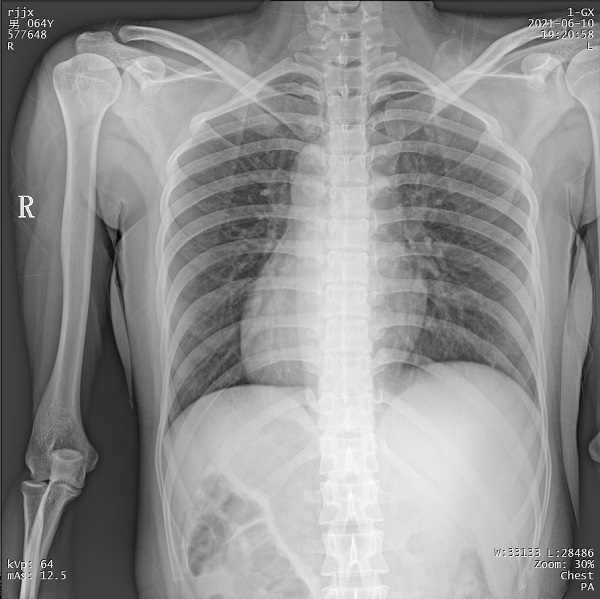

二、1ms 短時(shí)曝光 定格心肺運(yùn)動(dòng)瞬間影像

PLX5500系列移動(dòng)DR能夠在1ms的曝光時(shí)間內(nèi)輸出足量的X射線,獲取清晰圖像。特別適用于拍攝肺炎、塵肺病、肺結(jié)核等難以憋氣的患者,避免了因患者肺部呼吸運(yùn)動(dòng)而產(chǎn)生的運(yùn)動(dòng)偽影的影響,瞬間定格清晰圖像,以供醫(yī)生準(zhǔn)確診斷。